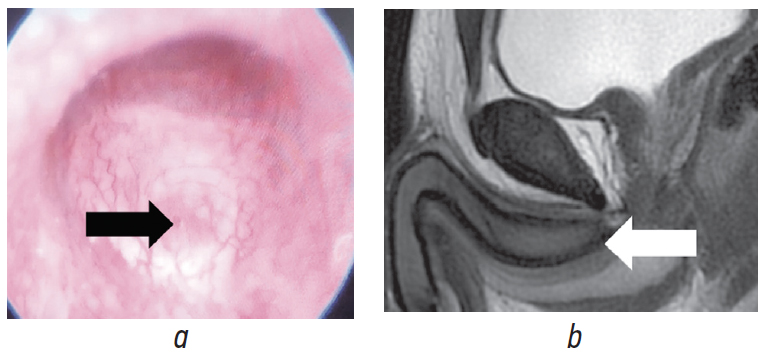

При уретроскопии в бульбозном отделе определялась передняя стенка сирингоцеле Купера, пролабирующая в просвет уретры (рис. 7).

Рис. 7. Уретроскопическая картина пациента Ш., 19 лет: а — передняя стенка бульбоуретральной кисты; b — перегородка в кисте (указаны стрелками)

Fig. 7. Urethroscopic picture of patient Sh., 19 years old: a – the anterior wall of the bulbourethral cyst; b – the septum in the cyst (indicated by arrows)

На основании проведенного дообследования установлен диагноз: «Закрытая бульбоуретральная киста».

После проведения консервативной терапии нестероидными противовоспалительными средствами и альфа-адреноблокаторами в течение месяца симптоматика регрессировала. При контрольном обследовании через 3 мес. по данным уретроскопии определялось точечное «окно» в мочеиспускательном канале — признак «открытого» сирингоцеле, а МРТ показала отсутствие ранее наблюдавшихся жидкостных образований (рис. 8).

Рис. 8. Пациент Ш., 19 лет: a — уретроскопическая картина (стрелкой указано «окно» опорожнившейся кисты); b — контрольная магнитно-резонансная томограмма малого таза без признаков кистозного расширения (стрелкой указано место ранее расположенной кисты)

Fig. 8. Patient Sh., 19 years old: a – urethroscopic picture of (the arrow indicates the “window” of the emptied cyst); b – control magnetic resonance imaging of the small pelvis without signs of cystic enlargement (the arrow indicates the place of the previously located cyst)

С учетом отсутствия симптоматики, «открытой» формы сирингоцеле Купера и молодого возраста пациент был выписан под амбулаторное наблюдение.